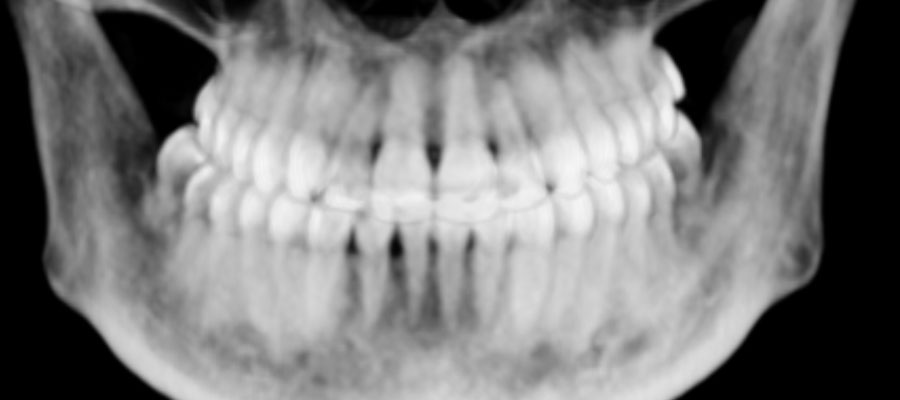

Caso clínico 2. La paciente presentaba Clase II dentaria división 2ª, con gran sobremordida, además de erupción ectópica de los caninos superiores. Se realizó ortodoncia multibracket transparentes con cirugía de fenestración de ambos caninos. Debido a la posición de éstos por palatino, colocamos dos microtornillos para ayudarnos en su tracción y poder separar la corona de las raíces de los incisivos. Posteriormente, traccionamos desde la cara vestibular con ayuda de un resorte para colocarlo en su lugar en la arcada.